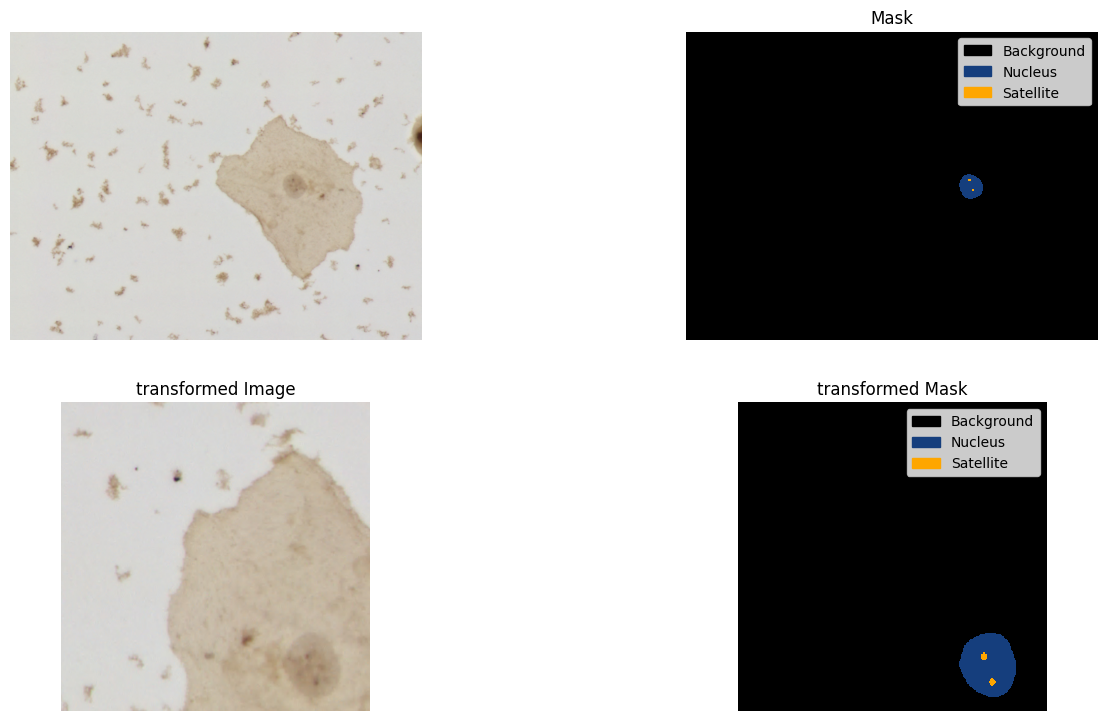

alb_transform = A.Compose(albumentations_transforms)Run the transforms pipeline and plot the image and mask as visualization example

image = np.array(dataset["train"][0]["image"])

mask = np.array(dataset["train"][0]["annotation"])

transformed = alb_transform(image=image, mask=mask)

transformed_image = transformed["image"]

transformed_mask = transformed["mask"]

fig = plt.figure(figsize=(16, 9), dpi=100)

ax1 = fig.add_subplot(2, 2, 1)

ax1.imshow(image)

ax1.set_axis_off()

ax2 = fig.add_subplot(2, 2, 2, sharex=ax1, sharey=ax1)

mask_categories = np.unique(mask)

colors_rgba = {k: tuple([c / 255 for c in v] + [1.0]) for k, v in id2color.items()}

cmap = mlp_colors.ListedColormap([colors_rgba[cat_id] for cat_id in mask_categories])

handles = [

patches.Patch(color=colors_rgba[cat_id], label=id2label[cat_id])

for cat_id in mask_categories

]

ax2.imshow(

mask,

cmap=cmap,

vmax=max(mask_categories),

vmin=min(mask_categories),

interpolation="nearest",

)

ax2.set_axis_off()

ax2.legend(handles=handles)

ax2.set_title("Mask")

ax3 = fig.add_subplot(2, 2, 3)

ax3.imshow(transformed_image)

ax3.set_axis_off()

ax3.set_title("transformed Image")

ax4 = fig.add_subplot(2, 2, 4, sharex=ax3, sharey=ax3)

ax4.imshow(

transformed_mask,

ax4.set_axis_off()

ax4.legend(handles=handles)

ax4.set_title("transformed Mask")Text(0.5, 1.0, 'transformed Mask')